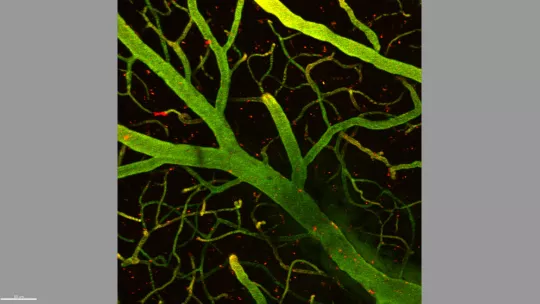

Una barrera de células controla estrictamente el paso de sustancias de la sangre al cerebro para protegerlo de agentes externos e infecciones. La valiosa función protectora de la barrera es a su vez un semáforo en rojo infranqueable para el 98% de fármacos candidatos a tratar enfermedades del sistema nervioso central. Científicos del Instituto de Investigación Biomédica (IRB Barcelona) han presentado hoy en un artículo en Angewandte Chemie una lanzadera hábil para traspasar la barrera hematoencefálica y transportar al cerebro diversas sustancias. El equipo de químicos del IRB Barcelona está ya estudiando su aplicación a necesidades médicas concretas. Junto a investigadores clínicos, están preparando terapias para el glioblastoma –el cáncer cerebral más agresivo en adultos-, la Ataxia de Friedreich –una enfermedad neurodegenerativa hereditaria- y próximamente para un tipo de cáncer cerebral infantil.

La barrera hematoencefálica no es totalmente hermética porque el cerebro ha de nutrirse constantemente de oxígeno, hierro, insulina, etcétera. Así que existen mecanismos de transporte a modo de puertas que se abren y se cierran continuamente. Aprovechando los receptores por los que el cerebro se abastece de hierro, la lanzadera-ambulancia consigue pasar sin entorpecer el paso de los nutrientes ni alterar la función protectora de la barrera. “Queríamos un vehículo que fuera sólo eso, un vehículo, y además que fuera pequeño -un péptido- y durable en sangre”, describe Roger Prades, estudiante de doctorado y primer autor de un estudio al que el equipo ha dedicado cuatro años de investigación en química de péptidos.